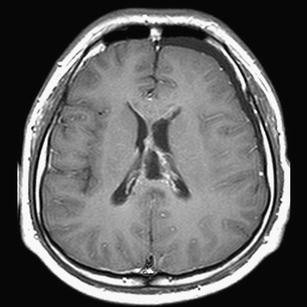

This case involves an 18-year-old man who presented with abnormal behavior, impairment in recent memory, and emotional change. Five years ago, he received five cycles of chemotherapy using cisplatin and ectoposide and 24G of local radiotherapy for clinical diagnosis of suprasellar germinoma in another hospital. The tumor was then completely resolute. Magnetic resonance imaging in our hospital revealed a large fatty mass located primarily in the septum pellucidum and some portions of the corpus callosum; a heterogeneous enhancing tumor was observed in the surrounding area. The second tumor was completely removed. The histological diagnosis was mixed GCTs containing the component of a germinoma and a mature teratoma.

Fig. 1